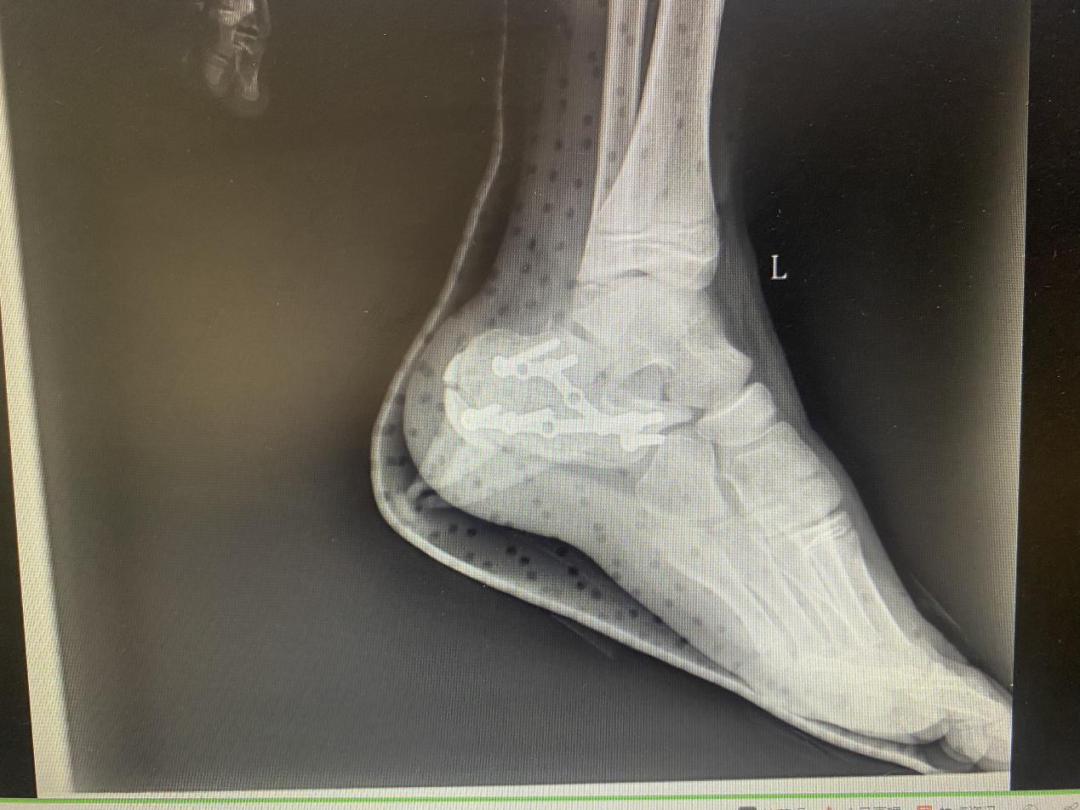

术后X线